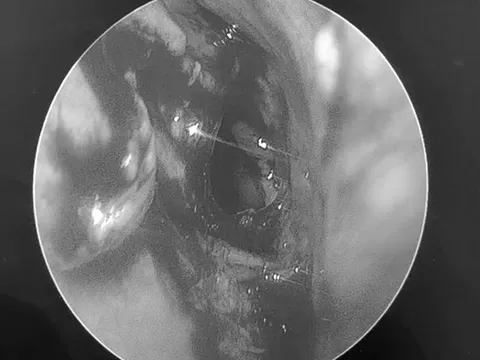

Bệnh nhân bị ù tai đến khám, bác sĩ bất ngờ phát hiện bệnh lạ

Một nữ bệnh nhân ở Cần Thơ bất ngờ bị tình trạng ù tai (theo nhịp mạch đập) từ khoảng 2 tháng nay, đã đi khám, điều trị nhiều nơi nhưng tình trạng ù tai không cải thiện, bác sĩ bất ngờ phát hiện bệnh lạ.